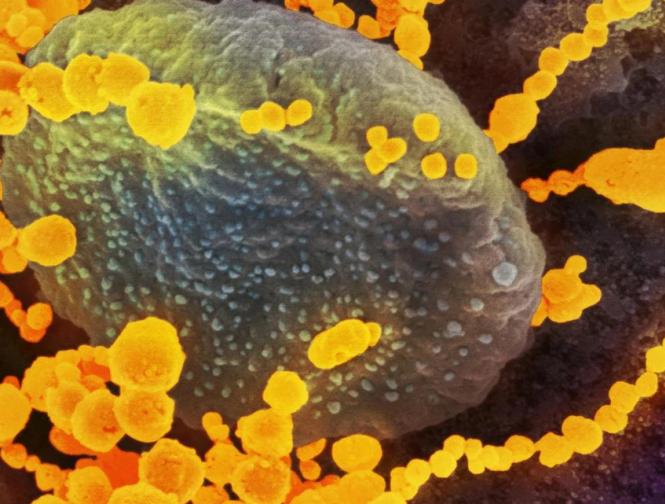

कोरोना व्हायरसने संपूर्ण जगभरात वर्षभरापासून हाहाकार पसरवला आहे. कोरोना व्हायरसच्या संक्रमणातून बाहेर आलेल्या लोकांसाठी एक नकारात्मक माहिती समोर येत आहे.

अमेरिकेतील टेक्सासमधील टेक युनिव्हर्सिटी ऑफ हेल्थ सेंटरच्या साहाय्याक प्राध्यापक डॉ. ब्रिटनी केंडेल यांनी केलेल्या दाव्यानुसार कोरोनावर मात केलेल्या लोकांना या आजाराच्या दीर्घकालीन परिणामांचा सामना करावा लागेल. तसंच त्यांची फुफ्फुसं स्मोकिंग करत असलेल्या लोकांच्या तुलनेत जास्त संवेदनशील होऊ शकतात.

कोरोनाच्या संक्रमणानंतर फुफ्फुसांवर तीव्र परिणाम होण्याची शक्यता असते. हा आजार उद्भवल्यास रुग्णाला श्वास घ्यायला त्रास होतो. हळूहळू रुग्णांच्या शरीरात ऑक्सिजनची कमतरता भासायला सुरूवात होते. अनेकदा या लक्षणांची कारणं कळून येत नाहीत.या कंडीशनला डॉक्टरर्स इडियोपॅथिक पल्मोनरी फायब्रोसिस असं म्हणतात.(ImageCredit- Aajtak)